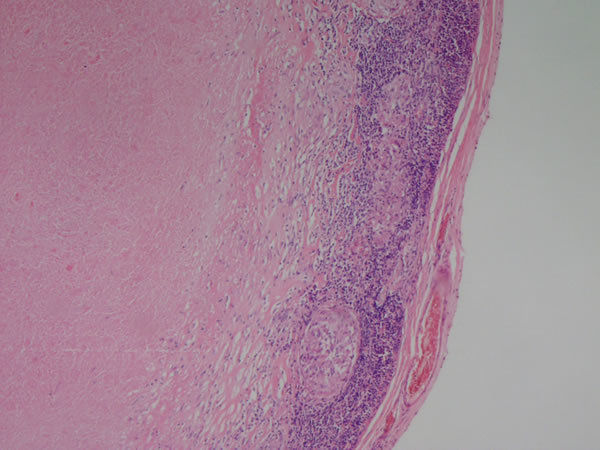

Linfonodo - tecido linfoide Necrose caseosa (parte rosinha no meio) - tuberculose ganglionar Causas: Histoplasmose, sarcoidose Outros achados: inflamação crônica (granuloma) |

Linfonodo -Tecido linfoide Necrose caseosa - tuberculose Outros achados: Infl. crônica - Granuloma epitelioide (rosinha, a parte roxa é normal) |

Linfonodo -Tecido linfoide Necrose caseosa (centro rosa)- tuberculose Outros achados: Infl. crônica - Granuloma epitelioide |